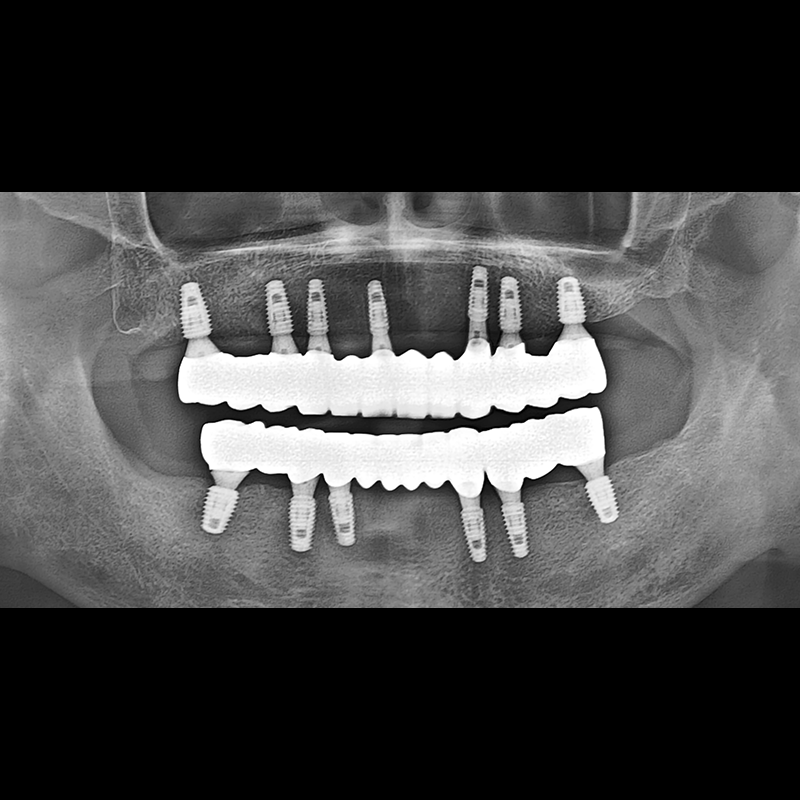

BEFORE AFTER

种植牙前后的照片 2025.05.30

在缺失的牙齿部分和难以挽救的牙齿位置植入了种植牙。